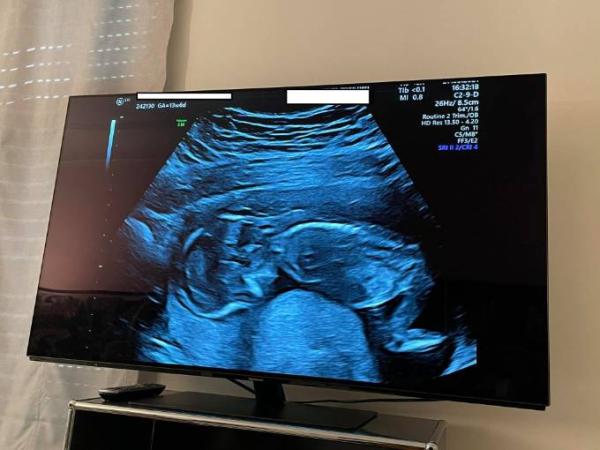

Hi ihr da :) Nachdem es im ersten Anlauf nicht geklappt hatte,ist meine Frau mittlerweile in der 15. SSW. Am Dienstag war Termin bei ihrer Gynäkologin, am Donnerstag hatten wir ersttrimesterscreening , nun so weit scheint alles in Ordnung zu sein, jedenfalls war dem Fötus im Ultraschall nichts ungewöhnliches anzusehen, andererseits sagte die Ärztin beim Screening das meine Frau nun doppelte Dosis Magnesium nehmen muss, weil sich die Gebärmutter entspannen soll, die Gynäkologin hatte am Dienstag im Ultraschall ein aktiven Fötus gesehen, der allerdings auf den Bildern ebenfalls eingeengt wirkte. Ihre Gynäkologin machte dazu aber keine angaben nur das alles gut aussieht, was uns auch beruhigt. Ich bin zwar im medizinischem Bereich tätig aber fern weg der gynäkologischen Medizin und meine Frau macht sich große sorgen, dass der Fötus sich nicht bewegen kann, ich hänge mal ein Bild an vielleicht interpretieren wir beide das einfach zu stark, ist sowas „normal“ ? also das der Fötus kaum Platz hat? Oder gibt sich das noch ? Ich denke mal wenn irgendwie was dramatisches wäre hätte man uns das ja sicher gesagt. Aber um meiner Frau nach der ersten vermeintlichen Windei-Schwangerschaft ihre angst zu nehmen frag ich mal hier nach :) Es gibt noch ein weiteres Bild wo man sich denkt das da doch mehr Platz ist aber ich kann hier nur ein bild anfügen. LG

Bild zu Gebärmutter sehr klein ? - Schwanger - wer noch? Rund um die Schwangerschaft